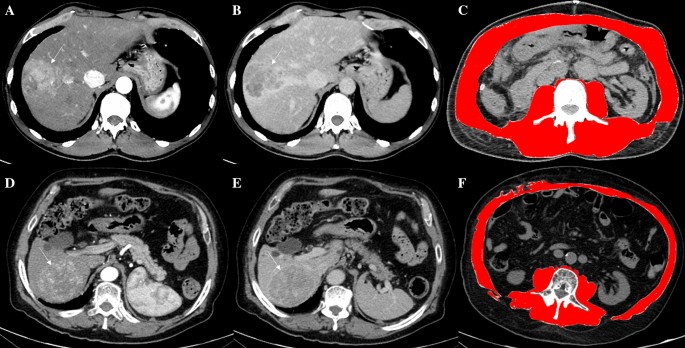

The usefulness of the assessment of the nutritional status in patients undergoing hepatectomy is known since 1994, when Fan et al. [17] studied two groups of patients randomly assigned to receive or not preoperative intravenous nutritional support (branched-chain amino acids, lipid emulsion and dextrose). The main difference found was a reduction in septic complication after surgery, the need of diuretic therapy to reduce ascites and less deterioration of liver function as measured by the change in the rate of clearance of indocyanine green ( – 2.8% vs.  – 4.8% at 20 min, p = 0.05), and more importantly a reduction of in-hospital mortality. As regards studies specifically addressing the role of sarcopenia in patients undergoing liver resection (summarized in Table 2), the first study evaluating the relationship between sarcopenia and the prognosis of patients with HCC following hepatic resection was made by Harimoto et al. in 2013 [18]. In this study, the cross-sectional areas of skeletal muscles (psoas, erector spinae, quadratus lumborum, rectus and transversus abdominis) in L3 region were normalized for height (cm2/m2) [18]. The cut-off values used for skeletal muscle associated with overall survival (OS) were defined, respectively, as 43,75 cm2/m2 for men and 41,10 cm2/m2 for women [7]. This study [18] concluded that sarcopenia was not associated with age, whereas it was significantly correlated with liver dysfunction as indicated by abnormal serum albumin levels and indocyanine green retention test (ICGR-15) values, as well as with reduced body mass index (BMI) values. Patients with sarcopenia showed a significantly impaired prognosis than those without, for overall (p = 0,001) and recurrence-free survival (p = 0,013). The first European study which evaluated the impact of sarcopenia on hepatectomy was reported by Voron et al. [20] in 2015. In this study, sarcopenia was defined as skeletal muscle index (SMI) (example in Fig. 1) less than 52.4 cm2/m2 for men and less than 38.9 cm2/m2 for women. Sarcopenia was correlated with the presence of a more undifferentiated HCC (p = 0.015) and the presence of satellite nodules (p = 0.031) than non-sarcopenic patients. Voron and collaborators [20] also showed that sarcopenia was a strong and independent prognostic factor for mortality (Hazard Ratio [HR] = 3.19, 95% Confidence intervals [CI] 1.28–7.96; p = 0.013) and recurrence (HR = 3.03, 95% CI 1.67–5.49; p = 0.001) after liver resection for HCC. These results were confirmed by a later study by Takagi et al. [22], which used a different cut-off to define sarcopenia, respectively, 46.4 cm2/m2 for men and 37.6 cm2/m2 for women, but they also found the overall 5-year survival rate after hepatectomy was significantly lower in the sarcopenic group compared to the non-sarcopenic group (58.2% vs. 82.4%, log-rank p = 0.0002) [22], moreover, they found that sarcopenia was correlated with the presence of microvascular invasions (p = 0.003) and the tumor stage (p = 0.015) [22].

The Computed Tomography images of two different patients (fist: a, b, c; second: d, e, f) demonstrated two large hepatic lesions consistent with hepatocellular carcinoma due to the arterialization (arrows in a and d) coupled with wash-out of contrast media in the delayed phases (arrows in b and e). The diagnosis was confirmed by histology after surgical treatments in both patients. The evaluations at the level of the soma of the third lumbar vertebra by using dedicated free software revealed no sarcopenia in the first patient (c) and sarcopenia in the second one (f)